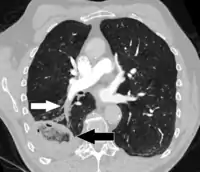

تصوير طبقي محوسب

التصوير الطبقي المحوسب للرئة والمصحوب باستخدام الصبغة المشعة في الوريد أصبح واسع الانتشار والاستخدام في تشخيص المرضى المشتبه بإصابتهم بالانصمام الرئوي، لهذا النوع من التصوير حساسية تبلغ 83% ودقة نوعية تصل إلى 96%.[39][40]

في الحالات التي يكون فيها الأفراد ذوي الخطورة العالية، هناك حاجة للمزيد من الاختبارات. يعتبر تصوير الأوعية الرئوية بالطبقي المقطعي المحوسب (CTPA) الطريقة المفضلة لتشخيص الانصمام الرئوي نظراً لسهولة إجراؤه ودقته.[27] على الرغم من أن تصوير الأوعية الرئوية بالطبقي المقطعي المحوسب مفضل، إلا أن هناك اختبارات أخرى يمكن إجراؤها.[25][28][29] على سبيل المثال، يمكن استخدام الموجات فوق الصوتية الضاغطة لاستقصاء أوردة الطرف السفلي القريبة.[27] يستخدم هذا الاختبار في المقام الأول كاختبار تأكيدي، مما يعني أنه يؤكد تحليلاً سابقاً يُظهر وجود أو اشتباه في وجود انصمام رئوي.[27] وفقاً لدراسة مقطعية، فإن التصوير بالموجات فوق الصوتية الضاغطة له حساسية 41٪ ونوعية 96٪.[27]